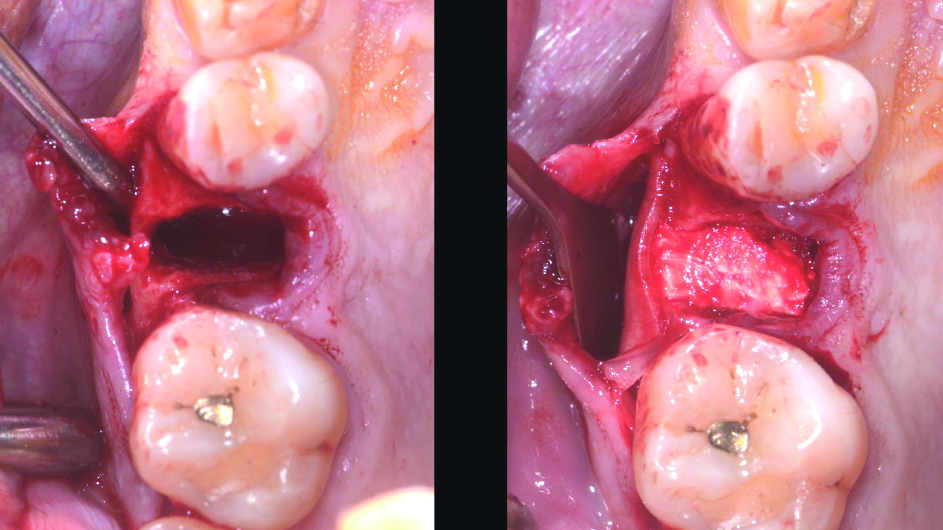

Il caso clinico riguarda un paziente con elemento dentale 14 fratturato, unitamente a fenestrazione vestibolare, estesa fino all’apice dell’elemento dentale, e riassorbimento palatale di 2 mm. L’intervento ha previsto l’incisione delle papille e lo scollamento a tutto spessore dei tessuti vestibolari estendendosi oltre la fenestrazione, con sollevamento del periostio, in modo da creare uno spazio per l’alloggiamento della lamina corticale. La lamina veniva opportunamente tagliata, per adattarla all’alloggiamento e veniva idratata con il sangue del paziente. La lamina veniva quindi incollata sul lato vestibolare, utilizzando gocce di colla di fibrina. A 4 mesi dall’intervento veniva effettuato l’esame CBCT, dal quale si evidenziava l’ottima rimineralizzazione dell’alveolo, con completo mantenimento del profilo corticale, chiusura completa della fenestrazione e assenza di riassorbimento osseo. Nel sito rigenerato veniva dunque posizionato un impianto 4 x 10 mm. Dopo ulteriori 3 mesi, l’impianto veniva protesizzato con pilastro Curvomax e una corona cementata in metallo ceramica. Il successivo controllo evidenziava una perfetta integrazione della protesi e un risultato estetico ottimale, con ripristino della fisiologica convessità vestibolare.